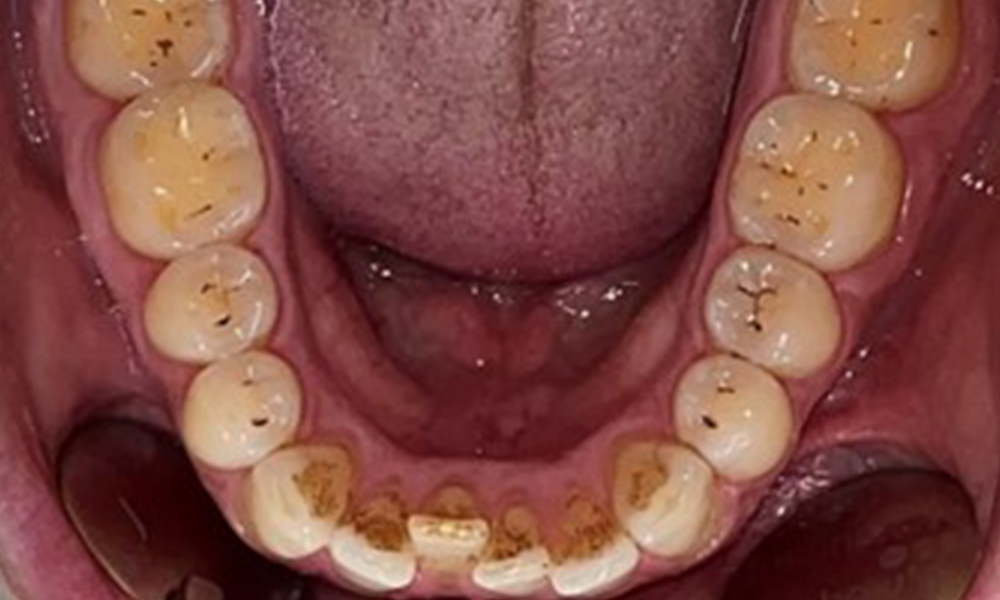

Dental zeigt sich ein vollbezahntes Gebiss mit 28 Zähnen. Auffällig sind Erosionen und Attritionen

(Abb. 4, Abb. 5). Der Patient trägt seit vielen Jahren nachts eine Schiene mit adjustiertem Aufbiss aufgrund Bruxismus. Die Erosionen sind auf den langjährigen Konsum isotonischer Getränke zurückzuführen. Parodontaler Knochenverlust und aktive kariöse Läsionen sind nicht vorhanden.

Es zeigt sich ein vollbezahntes, kariesfreies Erwachsenengebiss ohne radiologisch erkennbaren Knochenabbau (Abb. 6). Radiologischer Schmelz- und Höckerverlust sind insbesondere an 36 und 37 festzustellen.